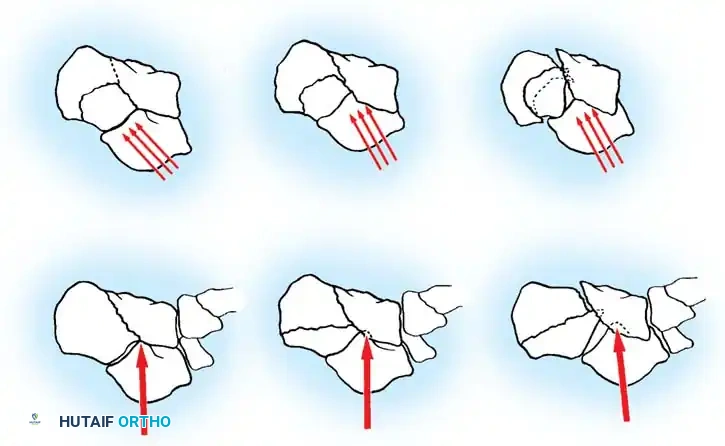

The Sanders classification has become the universally accepted system for intraarticular calcaneal fractures. It is based on the number and location of articular fracture lines seen on the semicoronal CT image showing the widest portion of the posterior facet.

The posterior facet is divided into three potential fracture lines (A, B, and C), creating four potential fragments (lateral, central, medial, and sustentacular).

* Type I: All nondisplaced fractures (regardless of the number of fracture lines).

* Type II: Two-part fractures of the posterior facet (one fracture line). Subdivided into IIA, IIB, or IIC based on the location of the line.

* Type III: Three-part fractures (two fracture lines), featuring a centrally depressed fragment. Subdivided into IIIAB, IIIAC, or IIIBC.

* Type IV: Four-part (or more) highly comminuted fractures.